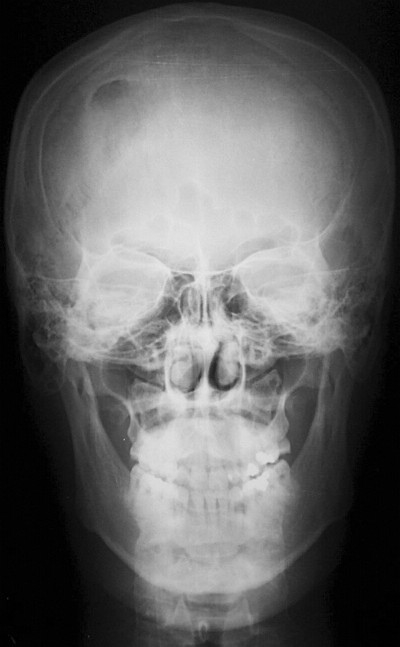

Обзорные рентгеновские снимки черепа свидетельствовали о наличии участка остеолизиса со склеротическими краями в правой лобной области (рис.1).

Рис.1. Обзорная рентгенограмма черепа: область остеолизиса лобной кости справа.